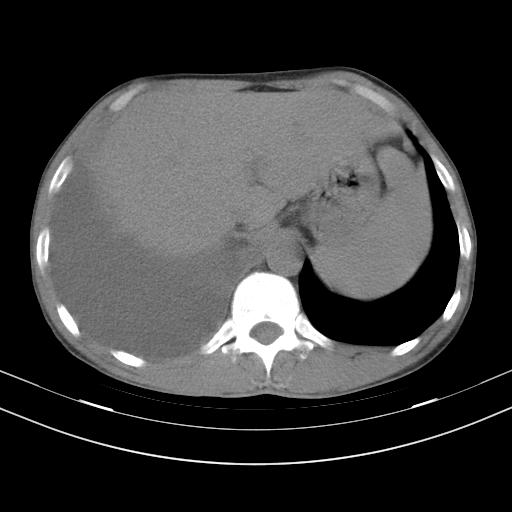

男性,44岁,结核病史多年。现胸闷气短,咳嗽,偶咳血。

右侧胸腔积液

右肺下叶不张

双肺多发结节影最分空洞形成考虑占位不除外结核

双肺陈旧性病变

1、右侧大量胸腔积液伴右肺压缩性膨胀不全,建议抽液治疗后复查 2、两肺继发性tb伴空洞形成。

1)两肺继发性肺结核伴空洞形成,左肺多发性结核球。2)右侧大量胸腔积液伴右肺部分膨胀不全。3)纵隔淋巴结肿大。